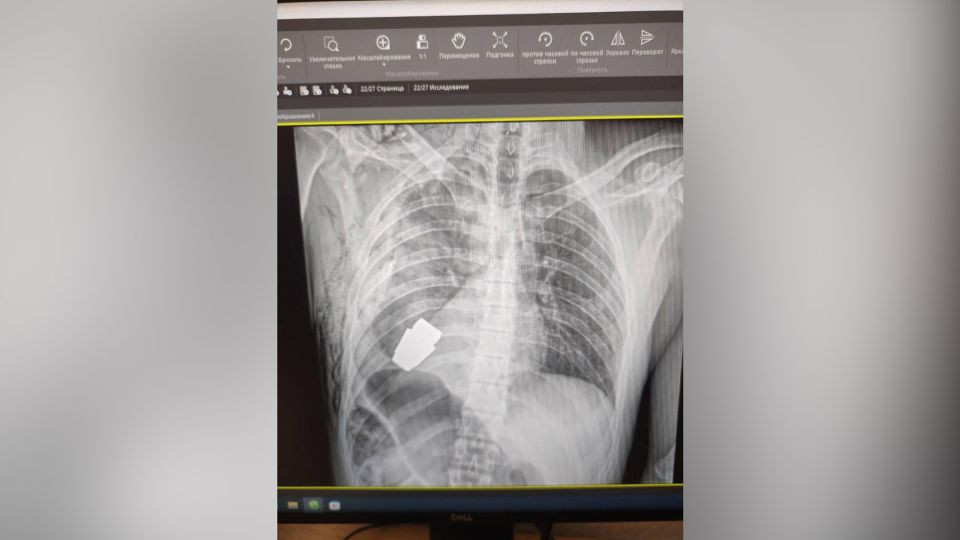

CNN đưa tin, hình ảnh chụp X-quang được lực lượng quân y Ukraine công bố cho thấy quả lựu đạn nằm ở phần thân trên của người lính.

Quả lựu đạn nằm trong lồng ngực của binh sĩ Ukraine. (Ảnh: CNN)

Quả lựu đạn nằm trong lồng ngừng của binh sĩ Ukraine được xác định là loại VOG dùng cho súng phóng lựu.